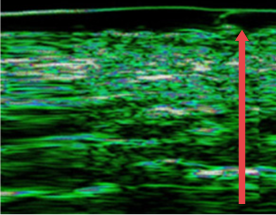

04. 皮肤真皮层厚度变化

可对因老化、频繁手术、外部刺激而变薄的皮肤真皮层进行改善

• radiesse_img11

施术前

• radiesse_img12

四个月后

(真皮层厚度增加12%)

• radiesse_img13

7个月后

(真皮层厚度增加27%)